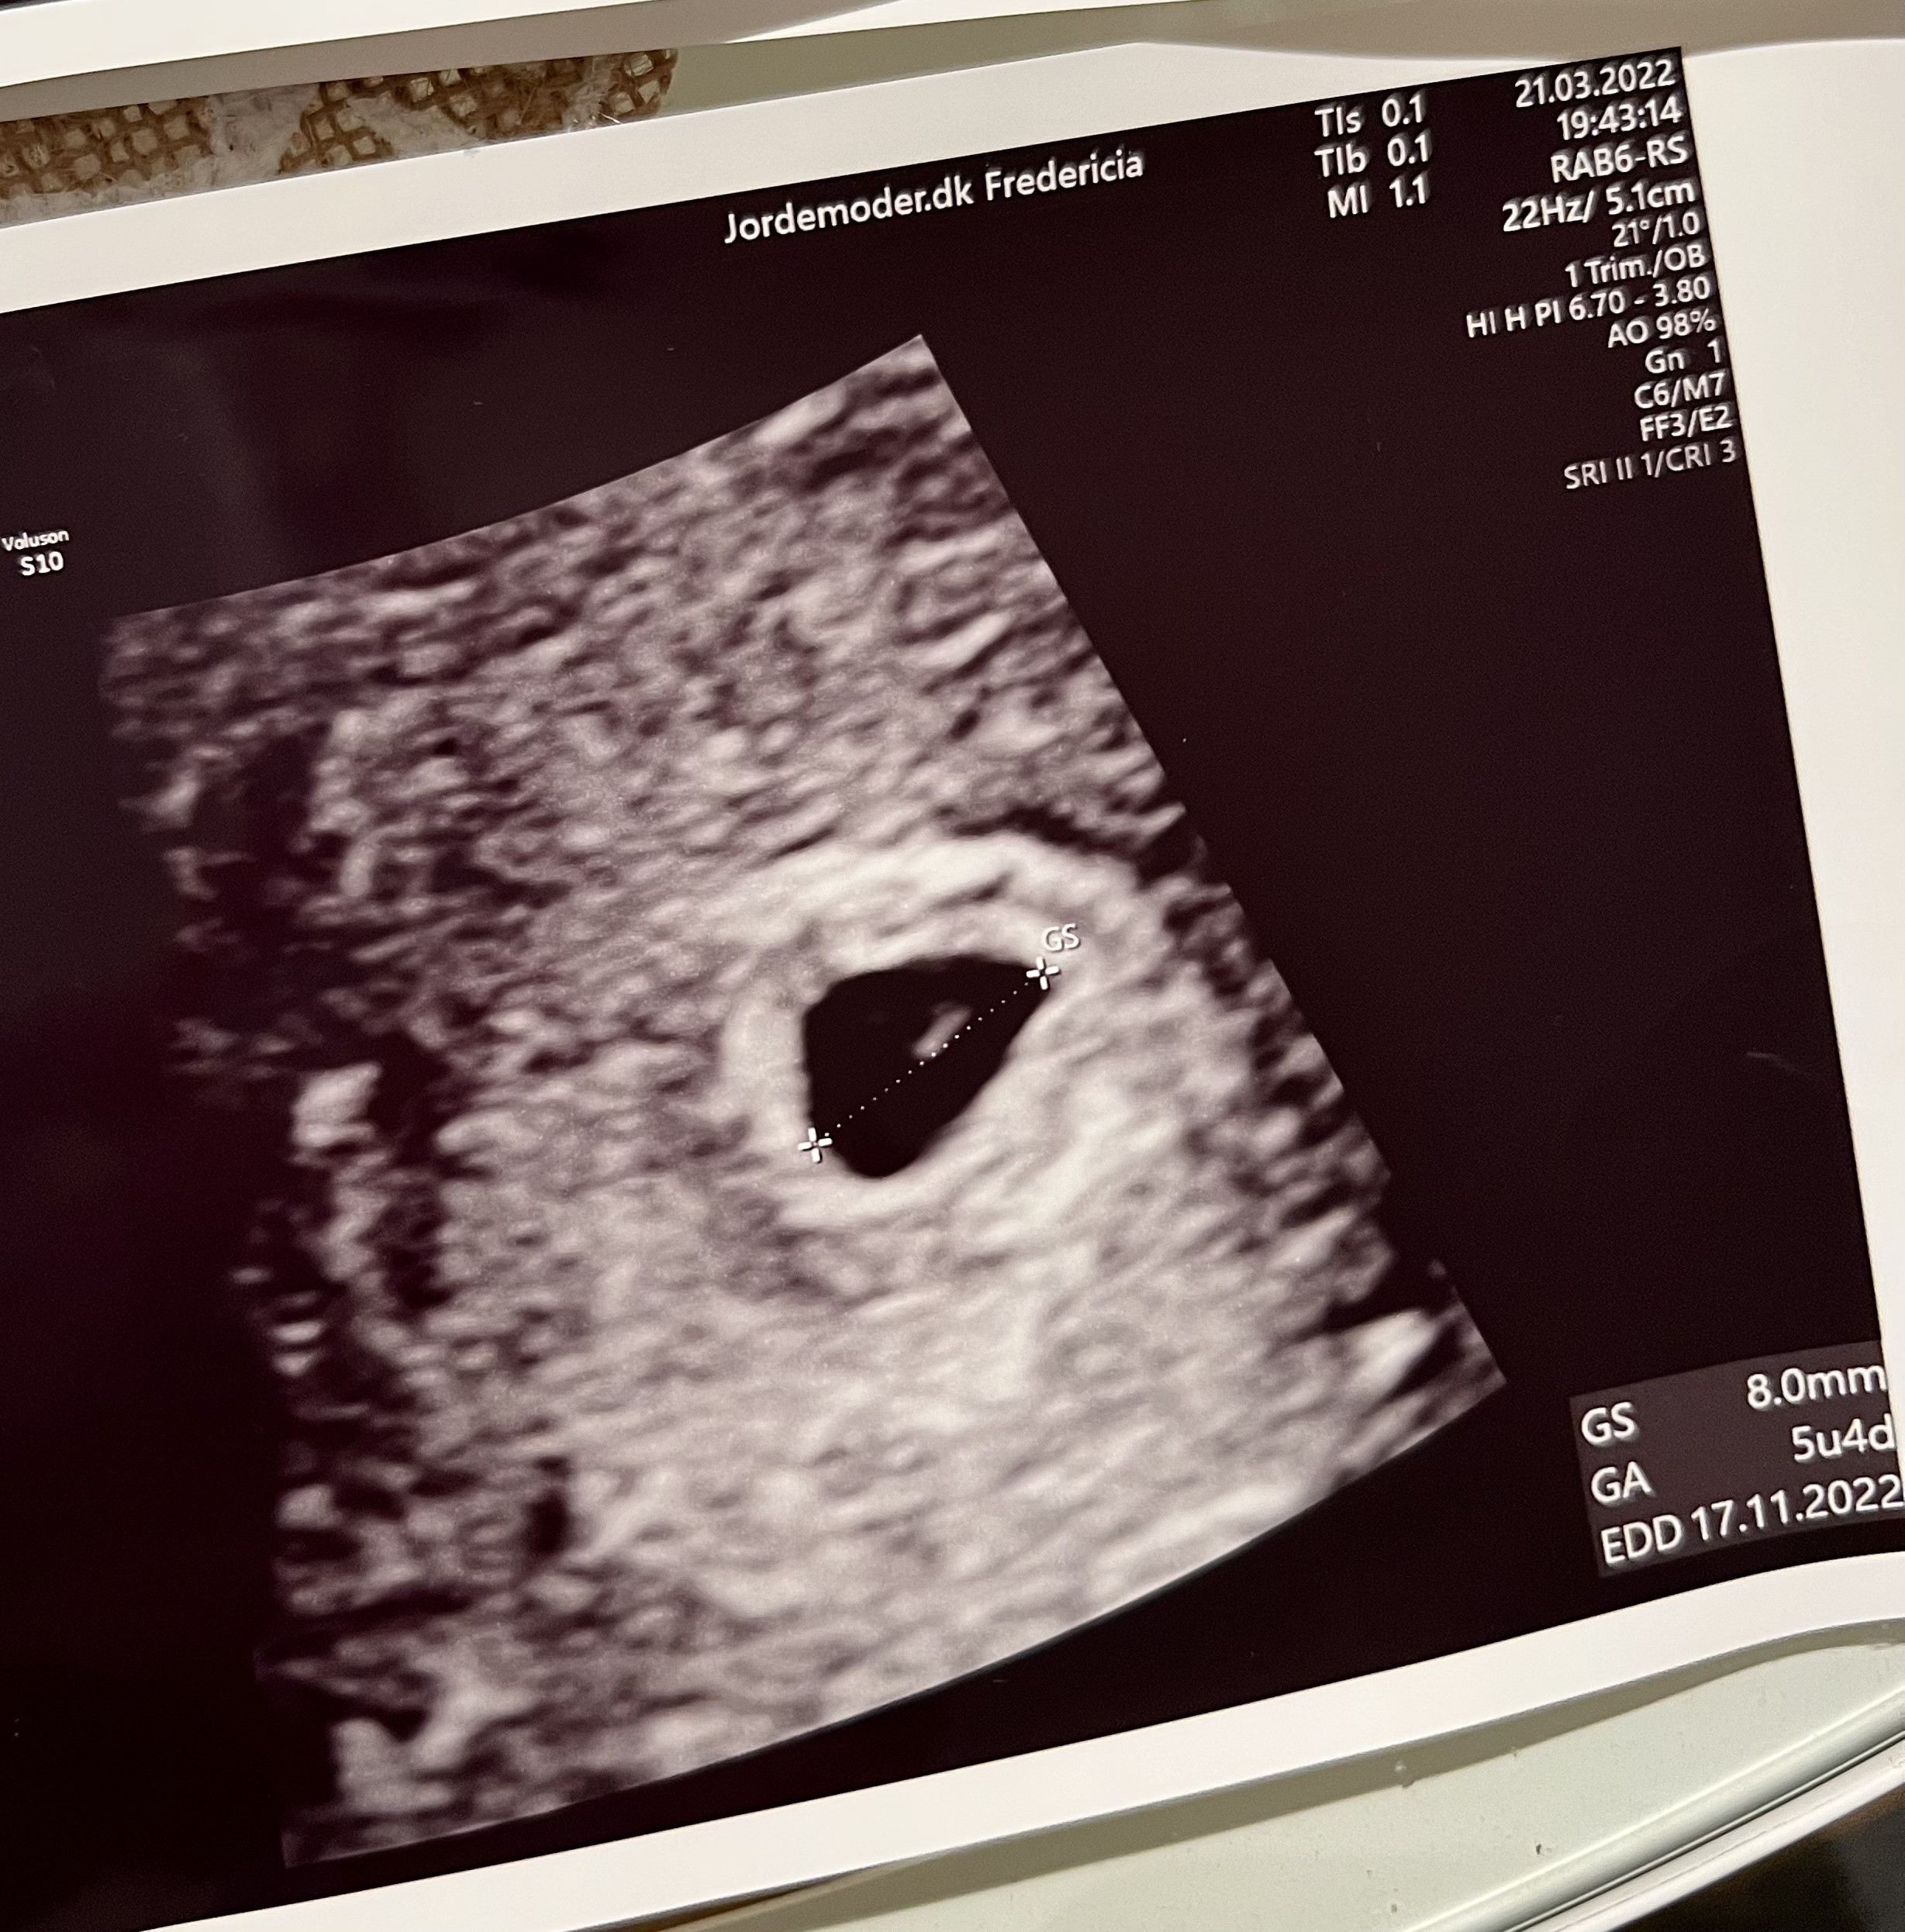

Byłam właśnie na usg! 😍 Ciąża wygląda w porządku, 8mm, 5+4 tc (wg aplikacji i ostatniej miesiączki 6+2), dobrze umiejscowiona, tylko oczywiście wczesna i mam wrócić za półtorej tygodnia 😂🙈👀. Jestem chociaż o tyle spokojna, że jest wszystko teraz w porządku 💪🏻❤️.